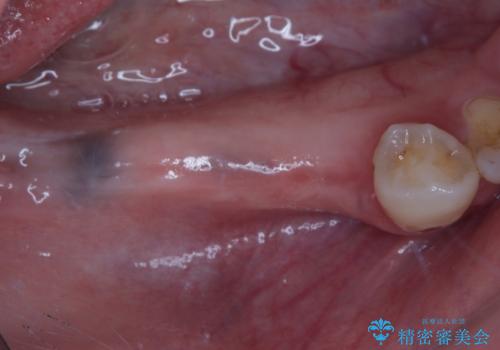

- ブリッジが装着されている奥歯がぐらぐらするとのことで来院された患者様です。

診察を行ったところ、手前の歯は歯根が破折しており、抜歯が必要な状態でした。

左右ともに臼歯部しか咬んでおらず、ブリッジの手前側の歯が破折したことで大きく揺さぶられてしまい、奥側の歯も周辺の歯が著しく吸収し、抜歯が必要な状態でした。

ブリッジの支台歯2本を抜歯し、反対側の咬合負担を軽減するために、通常よりも短い待機時間で2本のインプラントを埋入することとしました。